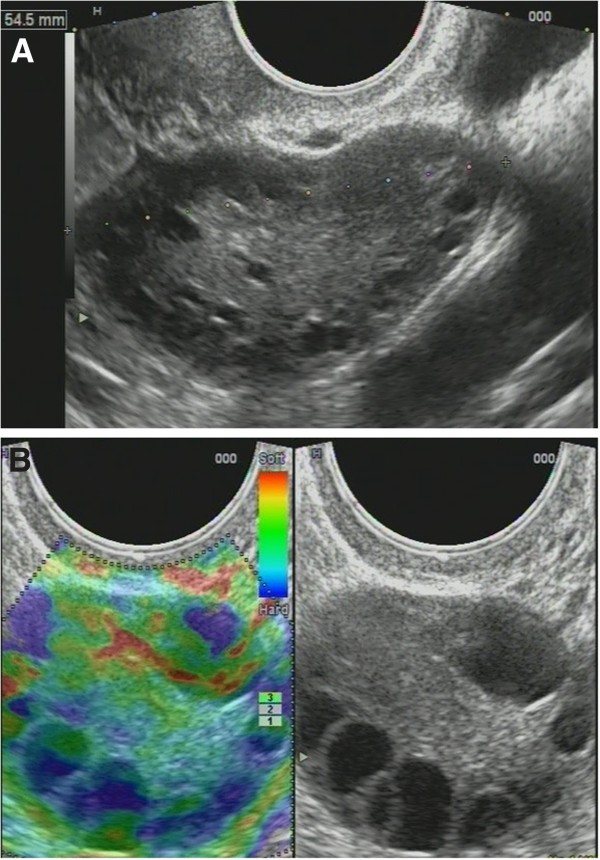

Non-homogenous and irregular margins were significantly higher in AEH than in both groups (P < 0.01). Mean M-echo thickness was found to be non-significant. Hypoechoic areas, hypervascularity on Doppler imaging, and stiffness (Figures 14 and 15) were more specific for AEH than for glandular cystic hyperplasia (P < 0.01, P < 0.01, P < 0.01, respectively; Figure 16). Fluid in the uterine cavity and BGR artefact were found to be specific for AEH (P < 0.01; Figure 17); BGR appearance correlated to the presence of fluid in the uterine cavity (r > 0.97; Figure 18).

Figure 16

Glandular cystic hyperplasia that is softer than the myometrium on SEG. E endometrium.

Figure 17

AEH endometrium ( E ) that is softer than the myometrium on SEG. Fluid inclusions and BGR artefact (+) are denoted by an arrow.